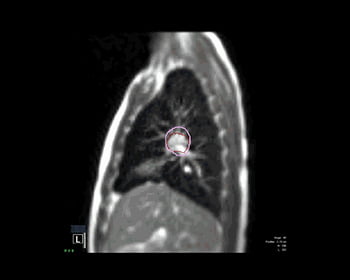

連続的MRI画像

MRIは、軟部組織の描出を得意とする画像法です。MRI技術は、CTのような電離放射線を用いず、肺などの生体内臓器のクリアな画像を提供します

完全MRIガイド即時適応型放射線治療システム MRIdianシステムは、常時MRIイメージング、放射線治療、ソフトウェアを統合した独自の放射線治療器です。MRIdianシステムを使用することによって、軟部組織を観察し、照射を視覚化して調整し、治療をコントロールすることが可能です。これらすべてを臨床上でリアルタイムに、侵襲的なマーカーを用いず、他の治療器では避けられなかった電離放射線の被爆なしに治療を行うことができます。